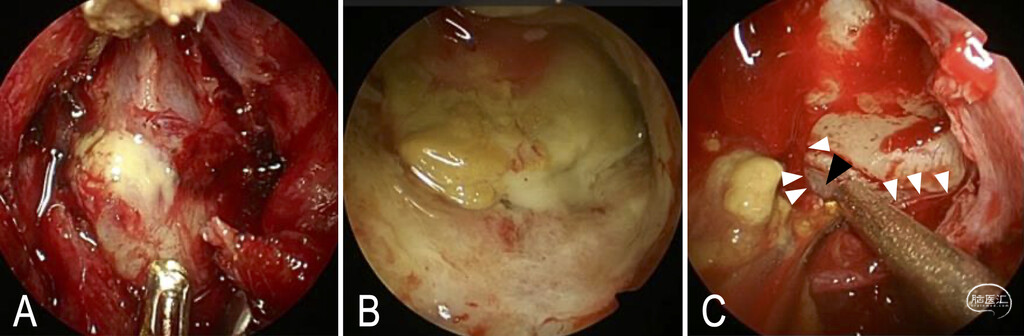

2.入路与显露:入院第6天,采用4毫米硬质内镜联合EndoArm机械臂(Olympus)行经鼻内镜囊肿开窗术,做双侧补救切口并切除鼻中隔后部,广泛开放蝶窦前壁后可见蝶窦内充满厚壁囊性病变(图3A)。

3.囊肿开窗引流:切开囊壁后有黄白色黏液样物质流出(图3B),结合术中所见确诊为蝶窦黏液囊肿,随后充分开窗囊壁并留取标本送病理检查,剥离囊壁时发现右侧鞍底及斜坡存在骨缺损,囊壁与鞍底硬膜紧密粘连(图3C),经蝶窦囊腔行多普勒超声确认右侧颈内动脉血流通畅,因囊壁与颈内动脉粘连导致剥离风险极高,故刻意保留粘连的囊壁组织。

图3:术中所见。A:黏稠的囊内容物经蝶窦前壁流出。B:囊腔与蝶鞍(鞍区)相分隔。C:囊壁(白色箭头尖示囊壁边缘)与硬膜(黑色箭头尖)紧密粘连。